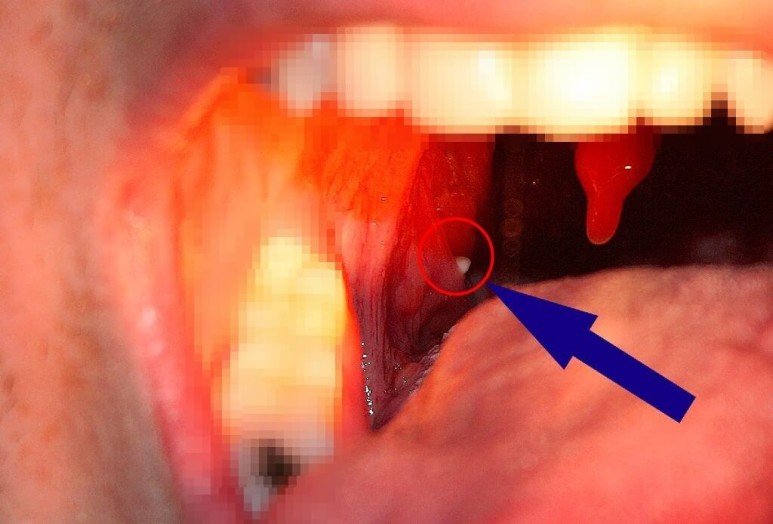

안녕하세요^ 무사하고 건강에 행복한 삶을 영위하고 싶은 생활건강 인플루언서 땡큐입니다.^^ 편도선에 생기는 악취를 가진 좁은 정도의 크기부터 손톱 정도의 크기까지 다양합니다.입 냄새를 유발하는 원인으로 구개편도선 표면에 존재하는 편도선이라는 부위에서 분비된 침소체가 구강 내 이물질과 섞여 생깁니다. 편도결석은 칼슘의 인산염과 탄산염으로 구성되어 있어 침 분비나 혀의 움직임에 의해 삼키거나 기침에 의해 반사적으로 외부로 나오게 됩니다. 편도결석은 보통 나쁜 냄새를 가지고 있어 휘발성 황화합물을 비롯한 악취를 유발하는 원인물질이 되고 식욕까지 변하기도 합니다. 심한 경우 병원에서 편도 구멍을 봉합하는 수술을 받아야 합니다. 그럼 편도결석의 원인과 증상, 편도결석을 빼는 방법에 대해 자세히 살펴보겠습니다.

편도선이 표면의 편도선이나 내부에 세균, 백혈구, 세균의 시체, 지방산, 음식물 잔류물 등이 쌓여 생깁니다. 자연적으로 배설되는 경우가 많은데 배설되는 편도선 표면의 출구나 소와 부분이 좁은 경우 편도선 내부 속에 굳어져 큰 몸이 될 수 있습니다.

편도결석증상

치주질환 등 치과질환이 없는 상태에서 입 냄새를 스스로 느낄 경우 편도결석일 수 있습니다.오랄크로마 등을 이용한 구취측정기로 휘발성 구취가스 분석도 진단에 도움이 되고 또한 지속적인 목 이물감을 호소하는 환자도 많습니다.